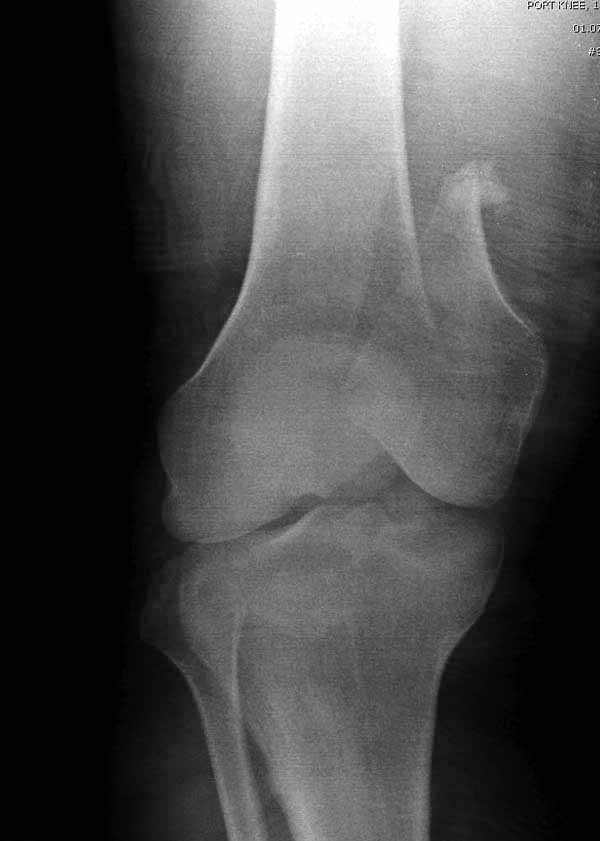

Однако в случае, представленном Константином Никитиным, не может быть применён ни ретроградный ни антеградный остеосинтез. Причина - нереально выполнить вышеуказанные необходимые требования, касающиеся дистальных блокирующих винтов. Из-за низкого перелома латерального мыщелка (перелом Hoffa) невозможно через него провести хотя бы 2 блокирующих винта, поскольку линия перелома мыщелка расположена либо на уровне верхушки межмыщелковой ямки либо незначительно проксимальнее. Поэтому авторам, с моей точки зрения, необходимо прислушаться к рекомендациям Джолдаса.

Антеградное штифтование не очень годится при переломах типа C3, когда есть многооскольчатость именно суставной поверхности. А при переломах типа C1 и С2, т.е. и в обсуждаемом случае тоже, он как раз вполне оптимален. На межфрагментарную компрессию как-то не приходилось так драматически полагаться при интрамедуллярном остеосинтезе, результаты хорошие без нее были.

Рационально ориентироваться на качественный аспект - проблема или решается, или нет. Переломы типа 33C1 или C2 (то есть без фронтального раскалывания мыщелков, как на показанной Вами томограмме) при обычном качестве кости успешно можно фиксировать гвоздями с фронтальными винтами. Получается, их прочностных характеристик уже достаточно.